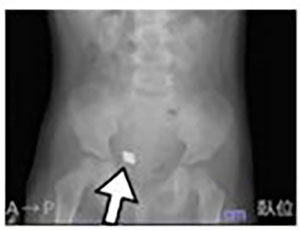

こどもが破損したおもちゃの部品を複数個誤飲し、負傷しました。(2021年 静岡県 2歳女児 重傷)

破損した玩具の磁石を誤飲した患者のレントゲン写真の例(事故事例とは別の事故のものです)

出展:日本小児科学会「Injury Alert(傷害速報)」

※2 このおもちゃは、ネオジム磁石が内蔵された樹脂製パズルで、対象年齢は 3 歳以上でした。